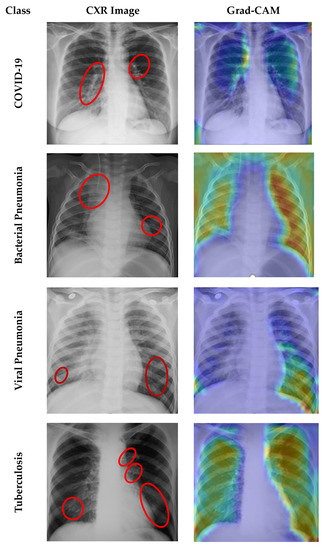

4.7. Grad CAM Visualisation

- Selvaraju, R.R.; Cogswell, M.; Das, A.; Vedantam, R.; Parikh, D.; Batra, D. Grad-cam: Visual explanations from deep networks via gradient-based localization. In Proceedings of the IEEE International Conference on Computer Vision, Venice, Italy, 22–29 October 2017; pp. 618–626. [Google Scholar]